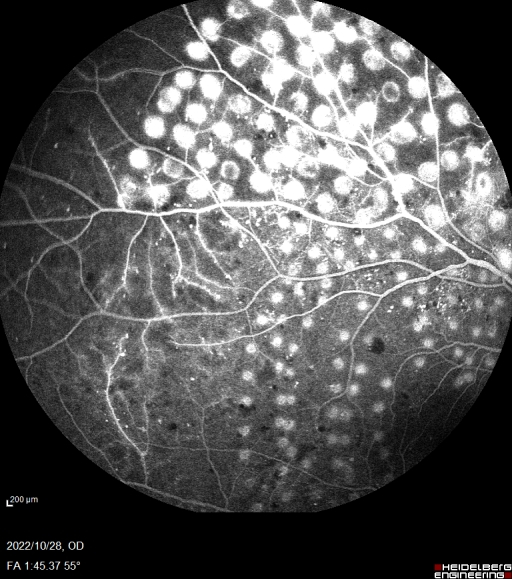

眼底血管造影是眼科临床上非常重要的检查方式,广泛应用于眼底血管疾病。海德堡共焦激光同步血管造影系统采用独特的共焦激光造影,只接受共焦平面的发射光,没有散射光干扰,可以获得高分辨率、高对比度的造影图像。同时基于共焦激光逐点扫描的特点和激光的高准直性,Spectralis HRA在小瞳下也可以获取高质量图像。可以同步进行FFA和ICGA造影,一次拍摄可将视网膜与脉络膜的血管造影实时同屏显示,方便临床医生进行同步对比观察,为诊断提供更全面和精准的信息。

此次合肥普瑞眼科医院引入的海德堡 Spectralis HRA共焦激光同步血管造影系统可配备有“天幕”102°超广角镜头,是造影设备的全新升级。102°超广角造影图像的观察范围更广,有效涵盖周边眼底,可以更早的发现早期糖尿病视网膜及一些血管性疾病的周边部改变,对于控制患者病情发展,减少视力损害意义重大。同时Spectralis HRA还具有动态造影的独特功能,每秒钟可以获取16帧高清图像,全程记录血管充盈过程,不遗漏重要细节。

10月28日,眼底病专科副主任张思伟利用海德堡 Spectralis HRA共焦激光同步血管造影系统顺利完成首例患者广角眼底血管荧光造影检查,为眼底病患者后续相关治疗提供有力支持,标志着合肥普瑞眼科医院眼底病专科诊疗水平再上新台阶。未来,合肥普瑞眼科医院将始终秉承“用爱传递光明”的理念,坚持以患者为中心,优化医院重点特色专科建设,全面提升医院各项诊疗服务水平,为人民群众的眼健康保驾护航!